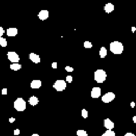

Additionally, two synthetic data generation methods between CycleGAN and SpCycleGAN from the same synthetic binary image are compared in Figure 4. Here, the synthetic binary image is overlaid on the synthetic microscopy image and labeled in red. It is observed that our spatial constraint loss reduces the location shift of nuclei between a synthetic microscopy image and its synthetic binary image. Our realistic synthetic microscopy volumes from SpCycleGAN can be used to train our modified 3D U-Net.